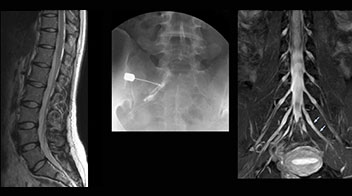

“In such case, we would then browse through axial T2-weighted MR images slice by slice and mentally reconstruct the actual situation based on both radiculography and MRI. Fortunately, NerveVIEW can now very well show nerve courses and presence of nerve compression or edema in one single image series.” “We have often seen NerveVIEW directly depict details of the nerve compression that were not observed by radiculography. Therefore, we think that with NerveVIEW we can reduce the number of invasive examinations, especially for some patients with lumbar plexus symptoms.”

“Before NerveVIEW, diagnosis by MRI alone was sometimes difficult, unless there was a strong suspicion based on clinical symptoms,” says Shoji Yabuki, MD, DMSc, Orthopedic surgeon at Fukushima Medical University School of Medicine. “This is why we routinely perform selective lumbosacral radiculography (nerve root block) and x-ray in such cases. However, radiculography can only depict nerves as far as the contrast agent reaches. When a nerve is distorted by compression, the contrast agent will not pass through this compressed area, preventing us from evaluating the full nerve compression.”

The key concept in MR neurography, Dr. Yabuki stresses, is the ability to directly visualize spinal nerves, versus inferring the presence of pathology indirectly. “Before NerveVIEW, we estimated compression of the nerve by looking for the presence or absence of fat signal on other MR images,” he says.

“For example, in sagittal images, when the presence of fat is observed in the intervertebral foramen, it suggests that there is a margin around the nerve. Similarly, the absence of fat indicates that the nerve is being compressed. So, we used to deduce nerve compression indirectly. With NerveVIEW, however, we can observe the condition of the nerves directly, regardless of the presence or absence of fat. We always prefer such direct observation of anatomy over having to make an inference about it.”